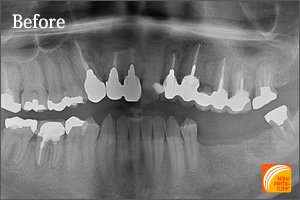

Before

期間 :3カ月

回数 :4回

費用 :410,400円

内容 :インプラント1本、GBR、セラミック冠1本分含む

After

右下奥歯に1本のインプラントを埋入した患者さんです。前後の歯の状態が良くないため普通のブリッジは適応不可でしたが、1本のインプラントを埋入することにより前後の歯の寿命を伸ばすことが可能になります。